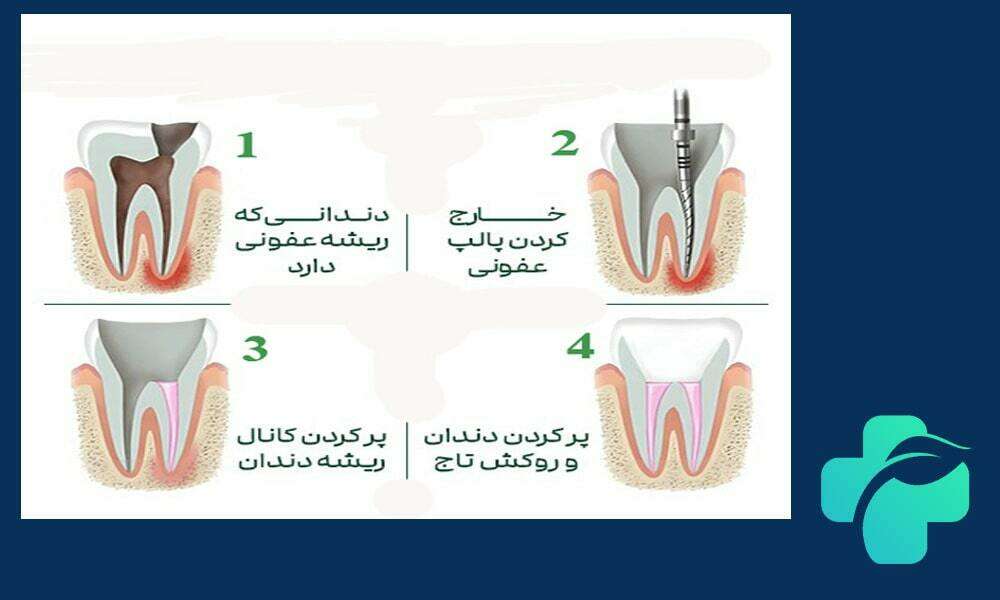

مراحل درمان عصب کشی دندان

درمان ریشه دندان معمولا توسط دندانپزشک متخصص با دقت بالا انجام می شود و شامل چند مرحله اصلی است:

- بی حسی موضعی: برای جلوگیری از درد، ناحیه دندان کاملا بی حس می شود.

- حفر حفره روی دندان: برای دسترسی به پالپ دندان، دندانپزشک با توجه به محل و وسعت آسیب، سوراخی روی دندان ایجاد می کند.

- پاکسازی کانال ریشه: با استفاده از ابزارهای مخصوص، عصب ملتهب یا عفونی تخلیه و کانال های داخلی تمیز می شوند.

- پرکردن کانال ها: پس از پاکسازی کامل، کانال ها با مواد مخصوص پر شده تا از ورود دوباره باکتری ها جلوگیری شود.

- ترمیم نهایی دندان: معمولا پس از عصب کشی، دندان نیازمند ترمیم با پرکردگی یا روکش برای بازگرداندن عملکرد و زیبایی است.

این مراحل با اصول علمی مشابه عصب کشی اطفال انجام می شود، با این تفاوت که در درمان دندان های شیری، از روش ها و مواد ملایم تر برای حفظ ساختار دندان استفاده می شود. رعایت دقیق هر مرحله، موفقیت درمان و جلوگیری از عوارض بعدی را تضمین می کند.